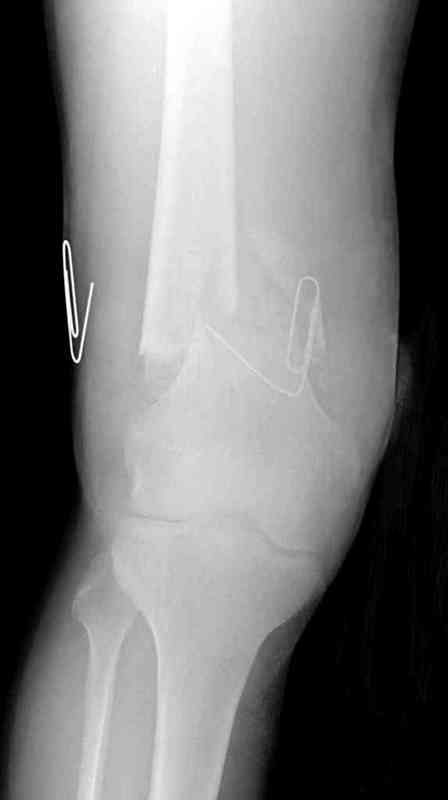

Укороченный фрагмент с самого начала являлся проблемным, на рентгене не видны следы от множественных спиц, обычно применяемых для лечения "коротких" переломов.

Адекватную фиксацию можно получить путем экстрафокальной косой остеотомии более проксимально, тем самым удлинить дистальный фрагмент, без повторной работы в фокусе патологии, что, в свою очередь, приведет к еще большему укорочению фрагмента.

Как предлагают коллеги, свежие стрессовые снимки уточнят наличие подвижности, а длинный на всю длину конечности снимок позволит провести точный предоперационный расчет по коррекции.